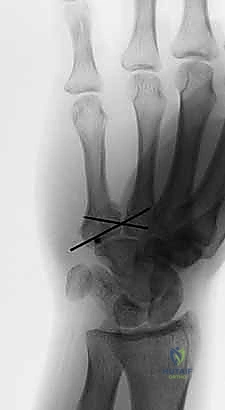

- صور الأشعة السينية المتخصصة (X-Rays): لا يكتفي الدكتور بالصور التقليدية، بل يطلب وضعيات تصوير خاصة (مثل الوضعية المائلة Oblique View بـ 30 درجة) التي تظهر قاعدة المشط بوضوح وتكشف الخلع الخفي.

الخطوة الثالثة: الرد المفتوح (Open Reduction)

يتم تنظيف المفصل من أي أنسجة محشورة أو شظايا عظمية صغيرة قد تعيق عودة المفصل لمكانه. ثم يتم إعادة العظم المخلوع والمكسور إلى وضعه التشريحي الطبيعي بدقة ملليمترية.

الخطوة الرابعة: التثبيت الداخلي (Internal Fixation)

وهنا تبرز مهارة الجراح. يعتمد نوع التثبيت على شكل الكسر:

* أسلاك كيرشنر (K-wires): أسلاك معدنية دقيقة يتم إدخالها عبر الجلد لتثبيت عظم المشط بعظام الرسغ المجاورة. تُزال هذه الأسلاك في العيادة بعد 4 إلى 6 أسابيع.